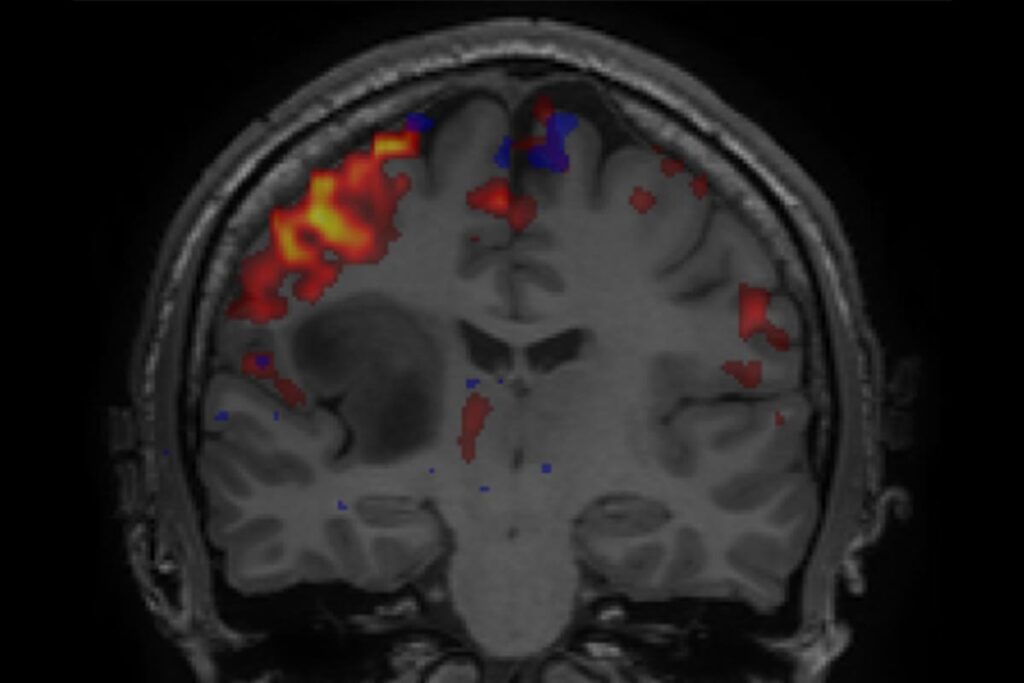

Hjernesvulster omfatter en lang rekke svulsttyper med ulike biologiske egenskaper. Det går et hovedskille mellom godartede og ondartede svulster, men det finnes mange forskjellige svulster i hver av disse gruppene. Diagnosene stilles basert på grundige bilde-, patologiske og genetiske analyser. Godartede svulster vokser typisk sakte og er velavgrenset til omkringliggende hjerne. Ondartede svulster vokser typisk raskt og kan ha et infiltrerende vekstmønster. Les mer hos kreftlex.no (ekstern link). Avansert bildeteknologi med fremstilling av svulst samt viktige funksjonelle områder i hjernen er svært viktig i diagnostikk og behandling. Bildet til høyre viser vanlig MR av hjernen med en ondartet hjernesvulst (mørkt område) og funksjonell MR av nærliggende områder som styrer bevegelse (farger).